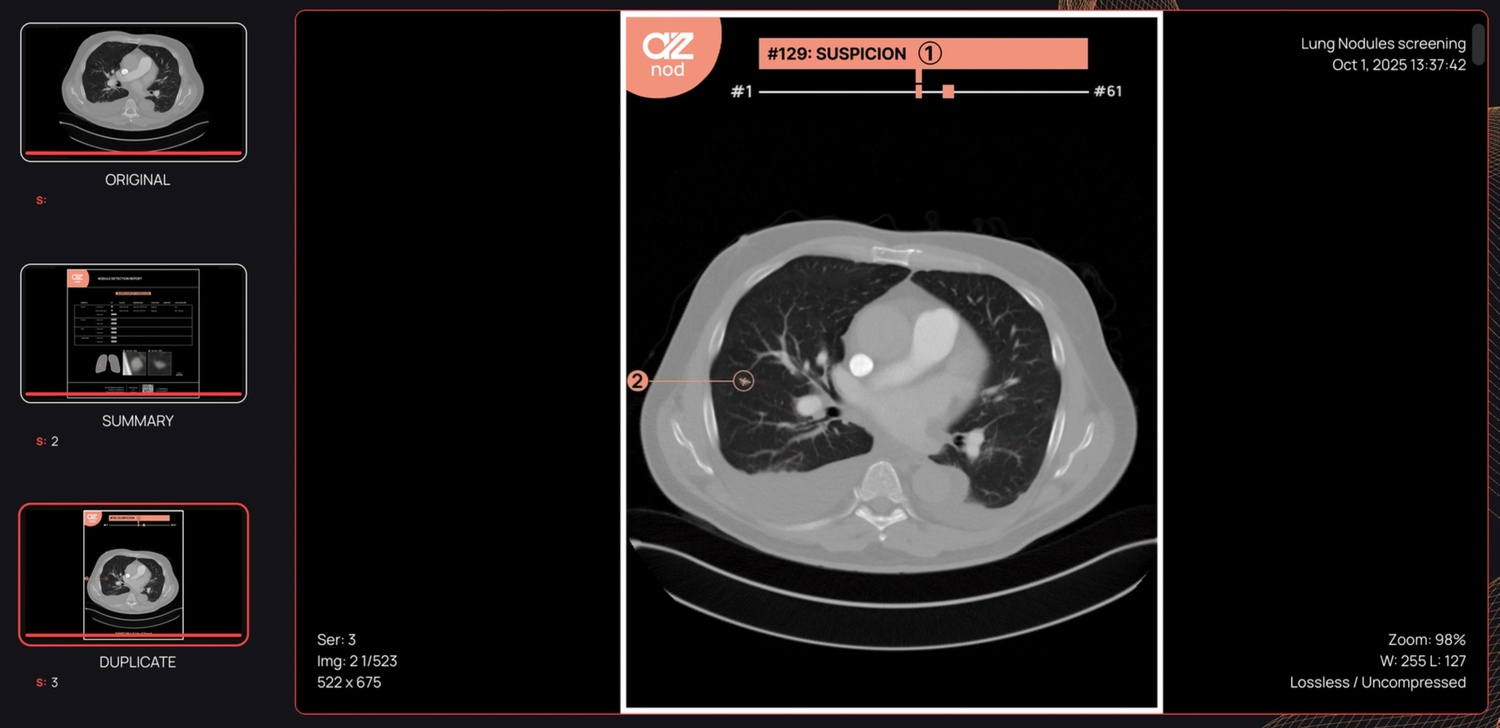

O AZnod analisa cada corte de uma TC para identificar nódulos entre 3 mm e 30 mm. O sistema avalia-os, mede o volume, o diâmetro do eixo longitudinal e os diâmetros perpendiculares, e indica os cortes exatos da TC onde eles aparecem. Em seguida, classifica os nódulos detetados de acordo com a densidade, a morfologia do contorno, a composição interna e o posicionamento nos pulmões, o que apoia a avaliação clínica alinhada com as diretrizes, sem alterar os fluxos de trabalho de diagnóstico existentes.

O modelo de IA processa imagens fortemente pseudonimizadas e retorna resultados radiológicos estruturados ao utilizador. O sistema fornece um único relatório listando cada nódulo por prioridade clínica, com vistas anotadas de tamanho e medições padronizadas em milímetros e milímetros cúbicos, juntamente com os seus atributos diagnósticos, bem como um esquema anatómico do pulmão destinado a permitir uma revisão rápida na avaliação dos nódulos.